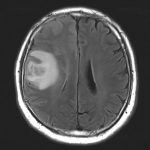

No.’25_108 手術前1

No.’25_108 手術前2